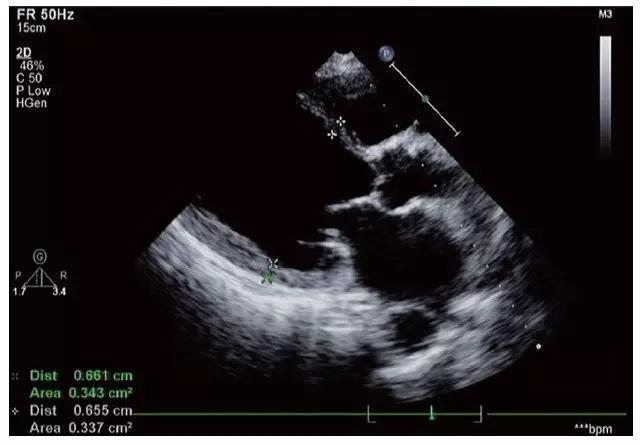

2.室间隔多数变薄,左心室后壁厚度正常或略薄,两者运动幅度均弥漫性降低,尤其以室间隔更为显著。室间隔运动幅度低于3mm,左心室后壁运动幅度低于7mm。心腔扩张较轻者,室壁厚度变化不明显,甚至有的可稍增厚。一般室壁厚度与左心室腔大小成反比,心腔越大则室壁越薄(图11-1-2)。

图11-1-2 扩张型心肌病心肌变薄